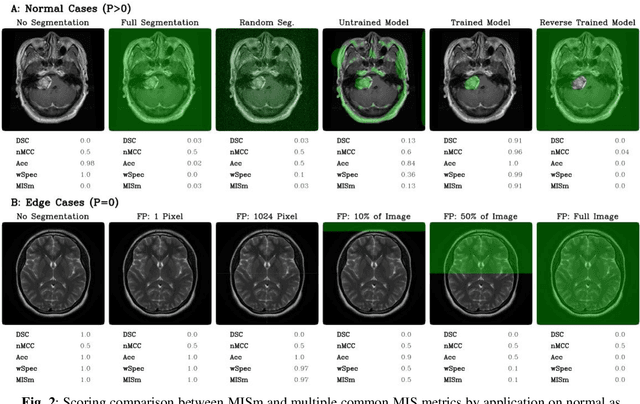

Abstract:Performance measures are an important tool for assessing and comparing different medical image segmentation algorithms. Unfortunately, the current measures have their weaknesses when it comes to assessing certain edge cases. These limitations arouse when images with a very small region of interest or without a region of interest at all are assessed. As a solution for these limitations, we propose a new medical image segmentation metric: MISm. To evaluate MISm, the popular metrics in the medical image segmentation and MISm were compared using images of magnet resonance tomography from several scenarios. In order to allow application in the community and reproducibility of experimental results, we included MISm in the publicly available evaluation framework MISeval: https://github.com/frankkramer-lab/miseval/tree/master/miseval